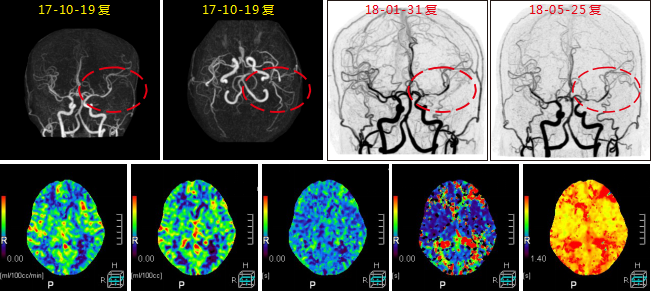

病例二 男,69歲, 于1月前無(wú)明顯誘因出現(xiàn)右上肢麻木不適, 此癥狀間斷存在, 持續(xù)數(shù)分鐘, 活 動(dòng)后好轉(zhuǎn)。 于1周前上述癥狀持續(xù)存在, 活動(dòng)后未見(jiàn)好轉(zhuǎn)入院檢查。

根據(jù)左側(cè)頸內(nèi)動(dòng)脈閉塞的長(zhǎng)度、形態(tài)以及側(cè)枝循環(huán)代償情況,考慮左側(cè)頸內(nèi)動(dòng)脈為慢性閉塞。

腦血流灌注圖可見(jiàn)CBF輕微下降,CBV略升高,MTT升高 ,TTP升高明顯。

640層寬體探測(cè)器CT灌注聯(lián)合CTA檢查,可在CTA掃描發(fā)現(xiàn)血管異常時(shí), 應(yīng)用CTP協(xié)助發(fā)現(xiàn)異常灌注區(qū), 對(duì)缺血的程度及代償情況進(jìn)行評(píng)估; 對(duì)照多時(shí)相血管CTA,找到責(zé)任血管, 評(píng) 價(jià)側(cè)支循環(huán); 兩者從形態(tài)學(xué)及功能學(xué)多方面對(duì)缺血性腦病進(jìn)行評(píng)估, 對(duì)臨床個(gè)性化診斷和治療具有重要指導(dǎo)意義。